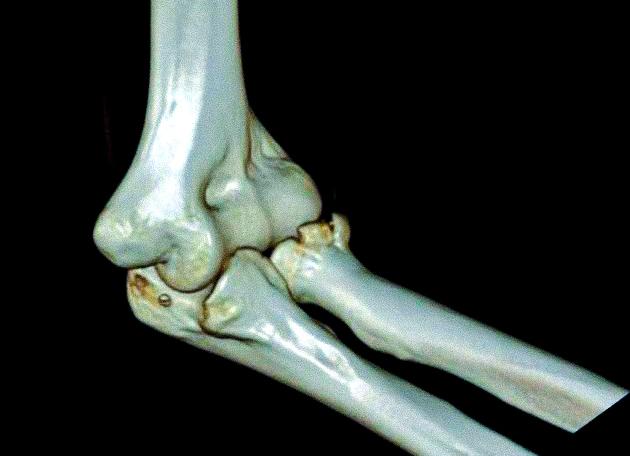

Мрт локтевого сустава

МРТ локтевого сустава: что показывает и как делают?

Этот диагностический метод имеет массу преимуществ, поэтому широко применяется во всех сферах медицины. Сущность МРТ заключается в воздействии магнитным полем на локтевой сустав и получении резонанса в виде радиосигналов.

МРТ локтевого сустава дает возможность получить точный результат исследования таких структур дистальной части плеча и проксимальной части предплечья: